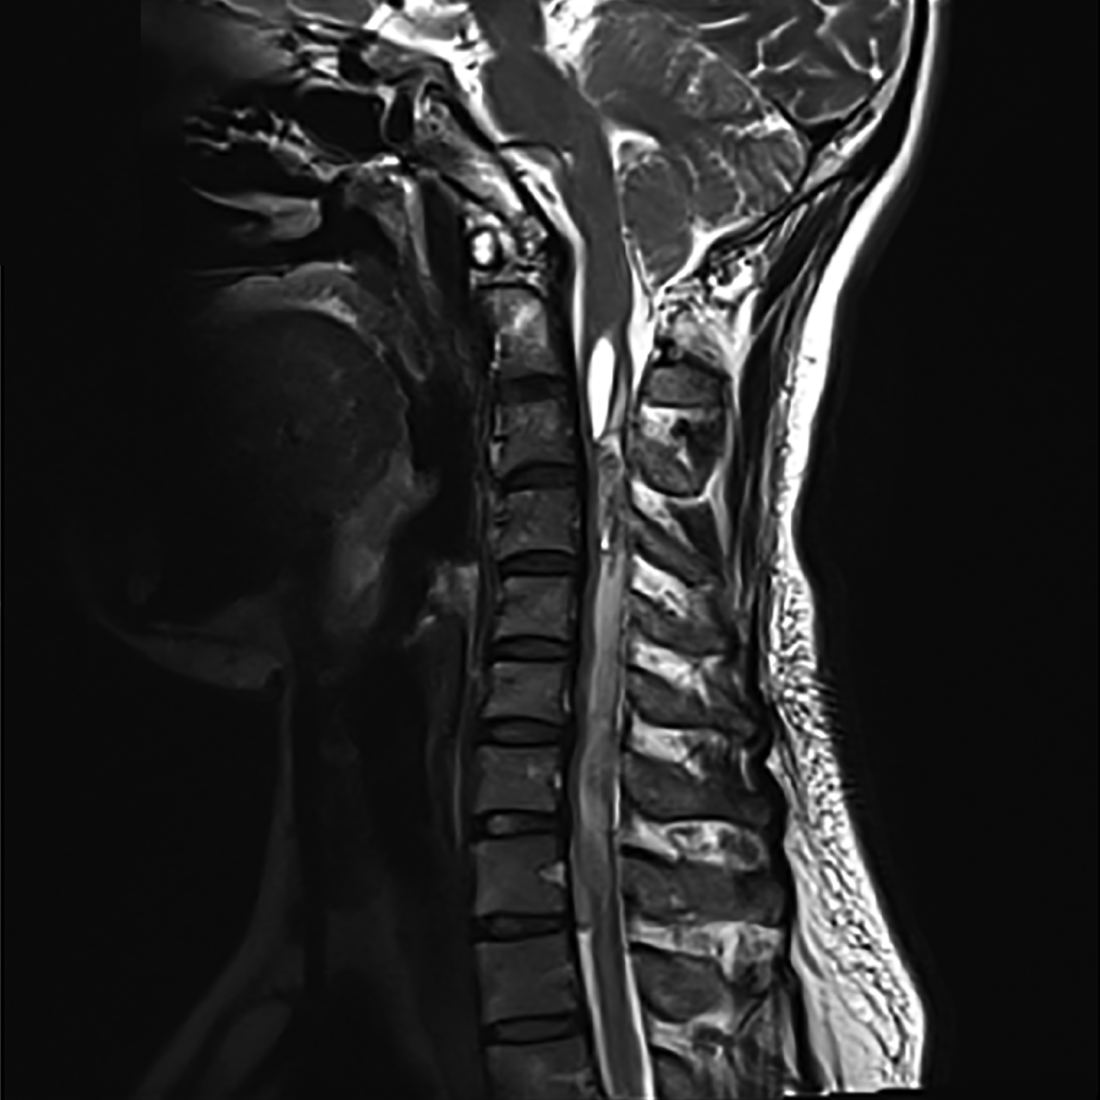

Needling necks and SCI 2025

Stimulated by Kim et al 2025.[1] SCI – spinal cord injury – key to acronym This paper was published in late August this year in the Korean Journal of Neurotrauma, but it has only just come up on my PubMed searches in the last week or so. It is not really extensive enough to devote … Continue reading Needling necks and SCI 2025

Post-acupuncture ACSEH

Stimulated by Wang et al 2025.[1] Photo by Gildo Cancelli on Pexels.com ACSEH – acute cervical spinal epidural haematomapaACSEH – post-acupuncture ACSEHSEH – spinal epidural haematomaIF – impact factorrTPA – recombinant tissue plasminogen activator – key to acronyms I thought this was going to be another first for the blog – a paACSEH mimicking a … Continue reading Post-acupuncture ACSEH